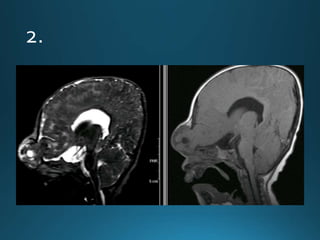

Sturge-Weber syndrome (SWS), or encephalotrigeminal angiomatosis, is a phakomatosis

characterised by facial port wine stains and pial angiomas

CT

detects subcortical calcification at an earlier age than plain film and can also demonstrate

associated parenchymal volume loss

'tram-track' subcortical calcification

MRI

T1: signal of affected region largely normal, with anatomic volume loss evident at older age

T1 C+ (Gd)

prominent leptomeningeal enhancement in affected area

T2

low signal in white matter subjacent to angioma representing

calcification later in life

abnormal deep venous drainage seen as flow voids

GE/SWI/EPI: sensitive to calcification, seen as regions of signal drop out